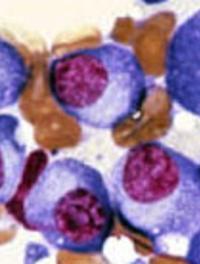

L'impact positif du triplet carfilzomib/dexaméthasone/daratumumab (KdD) en cas de myélome multiple en rechute ou réfractaire (MMRR) [...]

Le cocktail bortezomib/thalidomide/dexaméthasone (VTd) est le standard de traitement des myélomes multiples nouvellement diagnostiqués [...]

La survie du myélome s’est considérablement améliorée ces dernières années avec les inhibiteurs du protéasome et les immunomodulateurs [...]

Le traitement du myélome multiple a évolué depuis 15 ans avec, notamment, l’introduction des inhibiteurs du protéasome et des trithérapies [...]